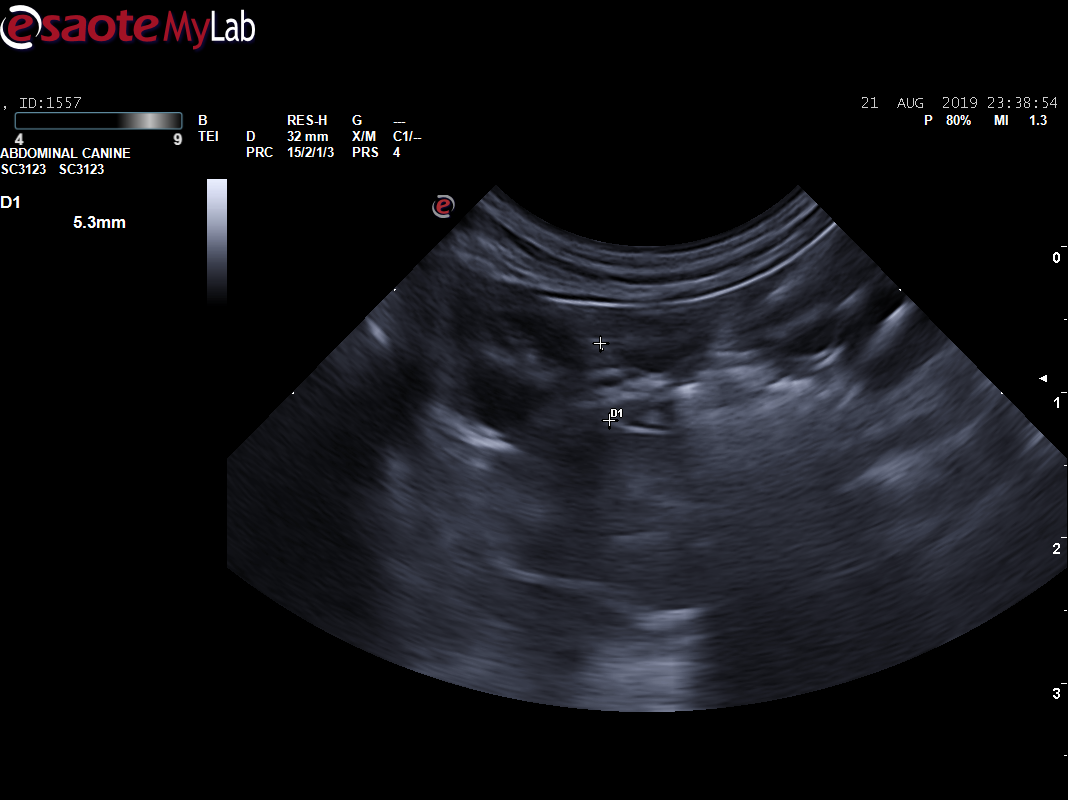

主人叙述2年前体检时,B超检查查出腹腔肿物(直径约6.1CM,场回声团块 ),主人当时选择保守治疗。每天吃完就吐,频繁的呕吐(3-4),导致梦龙体重急剧下降,主人十分担心。到我院初步诊断发现腹部触诊敏感,前腹部大肿物明显,为了准确评估梦龙的情况,医生对梦龙做了X光、生化和B超检查,进一步了解梦龙的身体情况。

B超显示:脾脏弥散性低回声(鉴别肥大细胞瘤、淋巴瘤、充血等),腹部肿物(鉴别淋巴瘤、肥大细胞瘤、肉瘤),肾脏(鉴别肾小球肾炎、慢性肾炎)。

经过5天住院治疗,住院期间患猫少量进食,未见呕吐、腹泻,多尿,水和良好,但仍有腹痛感。复查CBC,提示炎症未见下降;基础生化,提示应激;胸腔X线片,未出现转移情况,建议手术切除肿物送检。